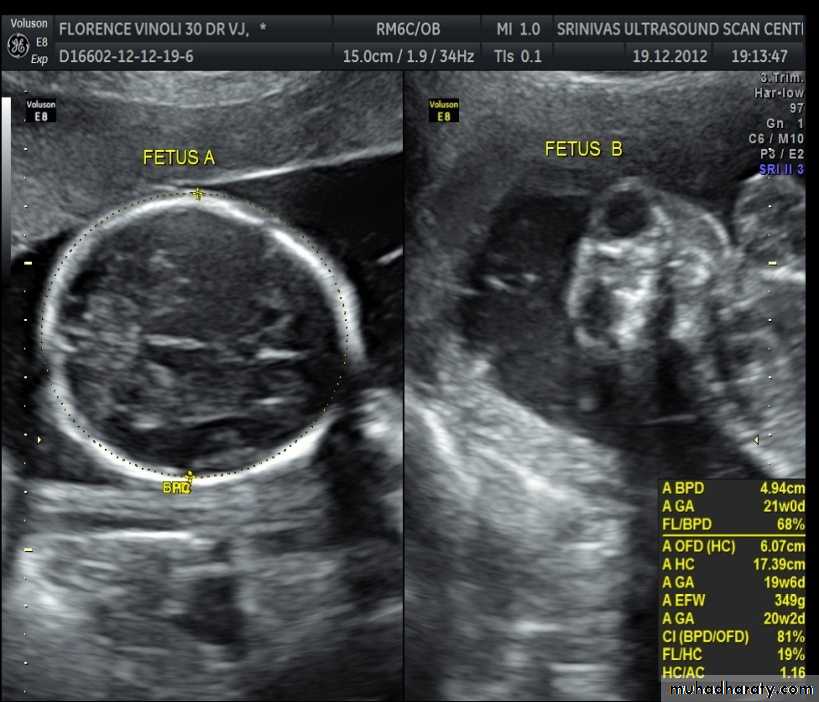

BPD together with head circumference (HC), abdominal circumference (AC), and femur length (FL) are computed to produce an estimate of fetal weight. In the second trimester this may be extrapolated to an estimate of gestational age and an estimated due date (EDD) .

The BPD should be measured on an axial plane that traverses the thalami, and cavum septum pellucidum. The transducer must be perpendicular to the central axis of the head, and thus the hemispheres and calvaria should appear symmetric.